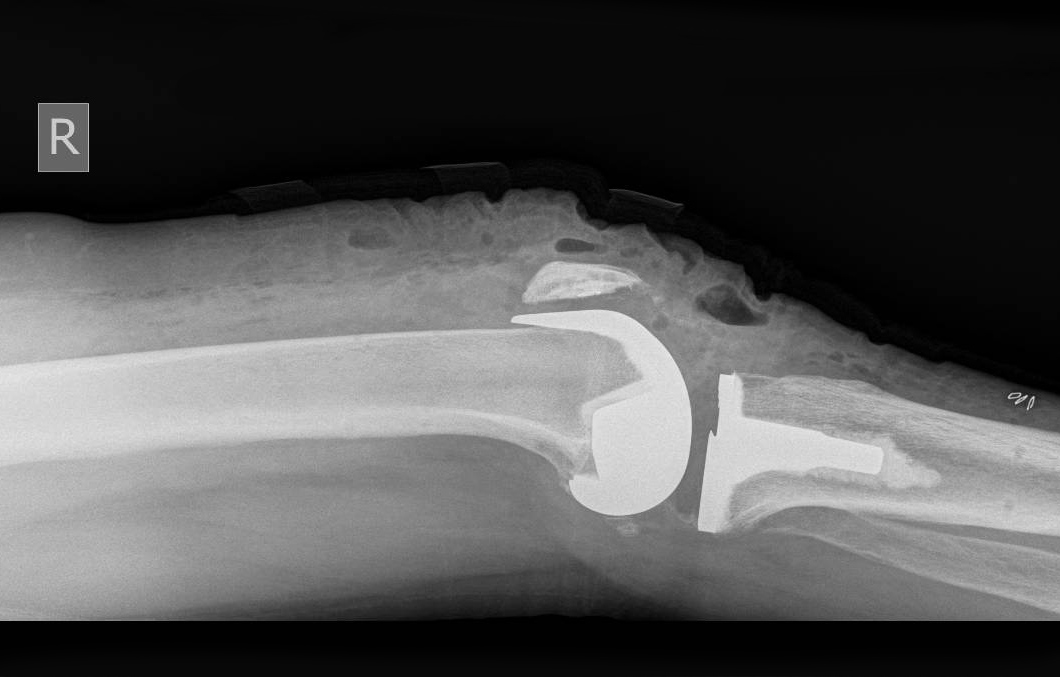

If the arthritis within the knee affects more than one compartment then a total knee replacement may be recommended.

Unlike other robotic systems with the CORI robotic assisted total knee replacement there is no need for further imaging scans such as a CT and therefore radiation exposure is reduced. During a CORI robotic assisted total knee replacement the knee is mapped during surgery using a probe. Tracers can monitor the movement and stability of the knee and an accurate 3D model of the knee is created by the robot. Using this information, the robot can display the optimal sizing and positioning for the implants to enable a balanced, full range of motion. With this level of accuracy, the longevity, function and feel of the knee implant can be improved.

Through a midline incision the surfaces of the bone can be replaced. The femoral component is a smooth metal component of varying sizes, which fits over the end of the femur. The tibial component consists of a metal base plate that sits on top of the tibia and a polyethelene (plastic) insert that fixes onto the tibial component. The patella surface may be replaced if it is worn. The implants are positioned and fixed to the bone using bone cement.